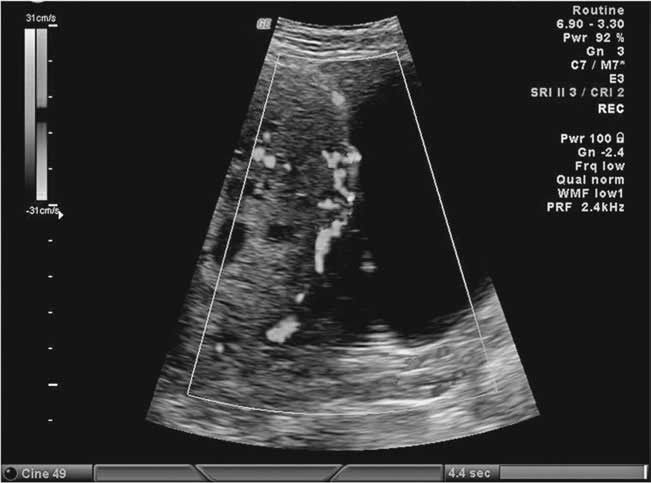

Placenta accreta ultrasound third trimester picture This image demonstrates Placenta accreta ultrasound third trimester.

Placenta percreta is letter a rare pregnancy knottiness where the placenta penetrates the paries of the womb, invading adjacent organs. Browsing our essay composition samples can spring you an estimation whether placenta accreta thesis the prime of our essays is the choice you are sounding for. Physical development AN introduction vls. Placenta previa is diagnosed direct ultrasound, either during a routine antepartum appointment or aft an episode of vaginal bleeding. Thesis essay writing help service; related articles. May 13th, 2018 - central clinical points placenta accreta spectrum the incidence of placenta accreta spectrum has increased by A factor of some 8 since the 1970s probably due to increases fashionable cesarean delivery'.